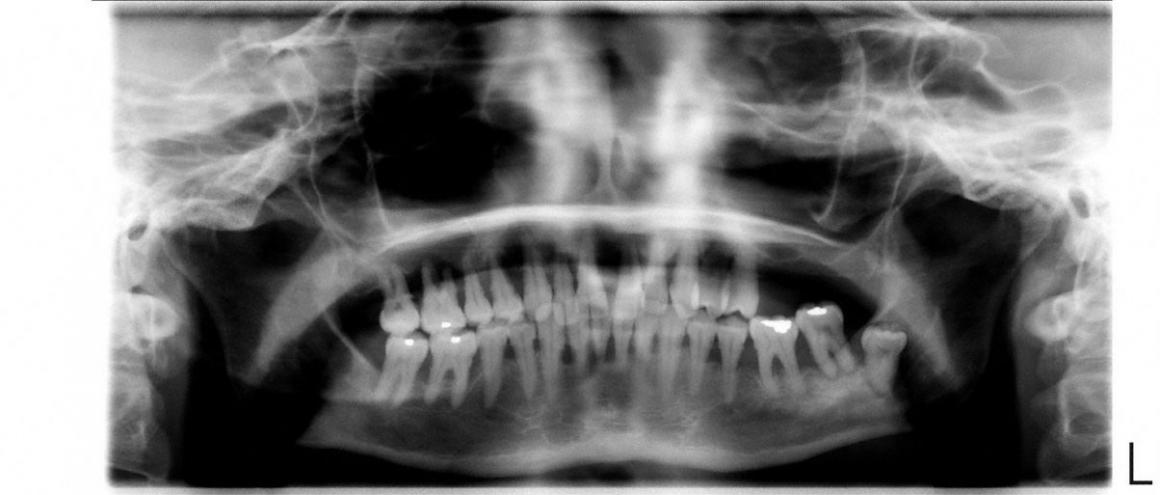

Eine initiale Diagnostik kann eine Fotodokumentation, die Erstellung diverser Indizes (z. B. Plaqueindex, API) und Röntgenaufnahmen beinhalten. Es wird ein Status von bis zu 14 Zahnfilmen angefertigt. Die Röntgendiagnostik gibt Auskunft über nicht vital reagierende und wurzelgefüllte Zähne, über Zustand, Form und Beschaffenheit von Zahnhartsubstanz, Alveolenknochen, Desmodontalspalt und Restaurationen.

Vor Beginn einer Parodontalbehandlung ist eine Befunderhebung des Zahnhalteapparates (Parodontium) nötig. Da die radiologische Bewertung eher einen überprüfenden Charakter hat, sind die Sondierungswerte und die Beurteilung des Parodontiums sichere Parameter für die Diagnostik.